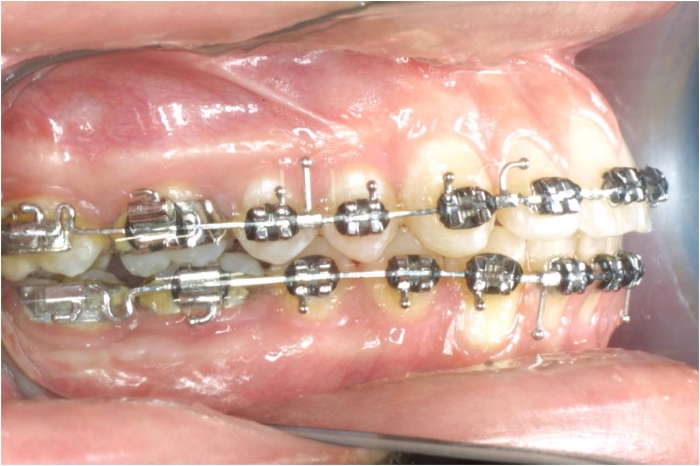

Mordida após cirurgia